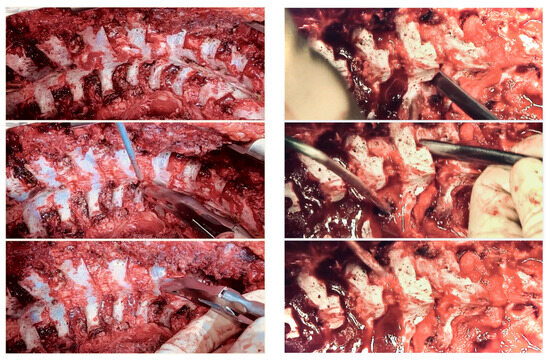

6. Anterior Release

7. Posterior Release

10. Rib Resection/Thoracoplasty